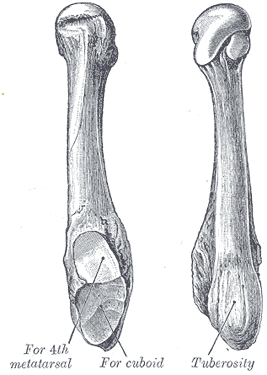

5th metatarsal tuberosity avulsion

The tuberosity avulsion fracture (also known as pseudo-Jones fracture or dancer's fracture[3] is a common fracture of the fifth metatarsal (the bone on the outside edge of the foot extending to the little toe).[4] This fracture is likely caused by the lateral band of the plantar aponeurosis (tendon).[5] Most of these fractures are treated with a hard-soled shoe or walking cast. This is needed until the pain goes away and then the patient can return to normal activities.[4] Healing is usually completed within eight weeks.[6]